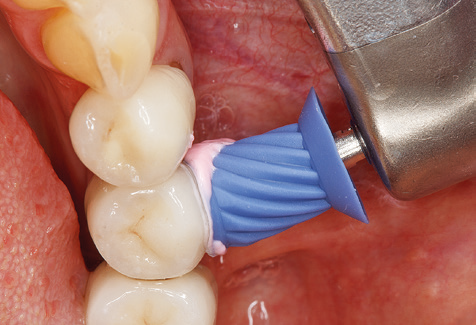

Following machine cleaning of the tooth and implant surfaces, the surfaces of the natural teeth are cleaned manually using standard hand instruments. When performing manual cleaning, particular attention must be given to maintaining the correct angle of application, appropriate sharpness, good support and working with the curette from apical to coronal. Either titanium or carbon curettes should be used for post-cleaning of the implant structures (Fig. 8). In addition to the use of ultrasonic devices, power jet devices can also be used in conservative dentistry. However, it must be taken into consideration that these procedures are not suitable for removing hard deposits and thus they cannot replace the use of hand instruments and ultrasonic instruments completely. In all cases, cleaning is followed by mechanical polishing of the accessible tooth and implant surfaces with polishing cups and polishing compounds (Fig. 9).

Fig. 4: Flexible probes with millimetre markings are recommended for the probing of dental implants (e.g. Colorvue Kit PCV11KIT6, Hu­Friedy). – Fig. 5a and b: A straight working tip (1P, W&H Dentalwerk Bürmoos GmbH) is a suitable instrument for use on all natural teeth. – Fig. 6: Curved working tips (3Pr/3Pl, W&H Dentalwerk Bürmoos GmbH) lend themselves to the processing of difficult-to-reach areas of the tooth and root surfaces (e.g. furcations). – Fig. 7: The tapered, hexagonal implant cleaning tip (1I, W&H Dentalwerk Bürmoos GmbH) permits atraumatic and efficient cleaning of the crown and abutment surfaces. – Fig. 8: Titanium and carbon curettes are suitable instruments for the manual cleaning of the implant surfaces.